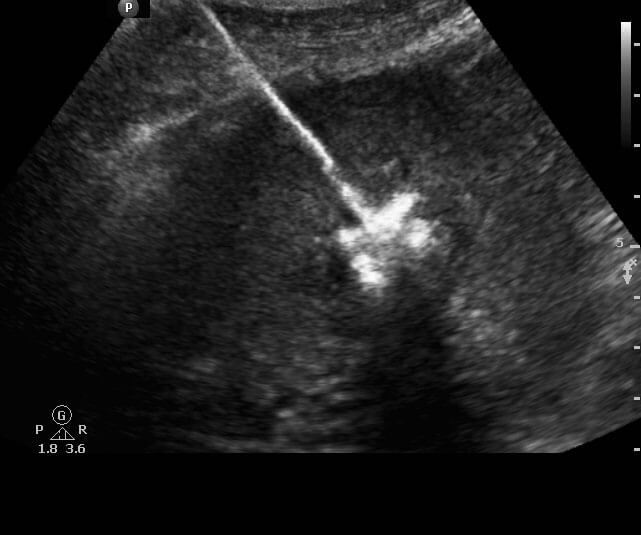

Ablation

Ablation is a treatment for primary and metastatic cancer involving the liver, lung, kidney, or bone. Ablation is a procedure performed by IR that involves placement of a needle-like probe into the tumor using CT or ultrasound for guidance. Once the probe is in place, the tumor is exposed to extremes of temperature; microwave and radiofrequency ablation expose the tumor to very high temperatures and cryoablation exposes the tumor to very low temperatures.